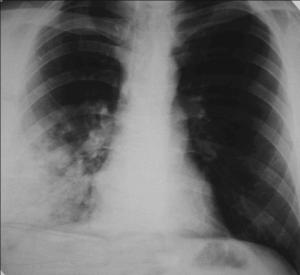

Внебольничная пневмония (ВП) - острое заболевание, возникшее во внебольничных условиях (вне стационара, либо диагностированное в первые 48 часов от момента госпитализации), сопровождающееся симптомами инфекции нижних дыхательных путей (лихорадка, кашель , отделение мокроты, возможно гнойной, боль в грудной клетке, одышка) и рентгенологическими признаками «свежих» очагово-инфильтративных изменений в легких при отсутствии диагностической альтернативы

(рис.1-1).

Рис.1-1.Внебольничная пневмония с локализацией в средней и нижней долях правого легкого.

Рентгенологический признак пневмонии – инфильтративное, обычно одностороннее затемнение легочной ткани, которое может быть очаговым, сливным, сегментарным (рис.1-2), долевым (обычно гомогенным) и тотальным. Рентгенологическое исследование следует проводить в двух проекциях – задне-передней и боковой. При выполнении исследования следует оценить распространенность инфильтрации, наличие или отсутствие плеврального выпота и полости деструкции.